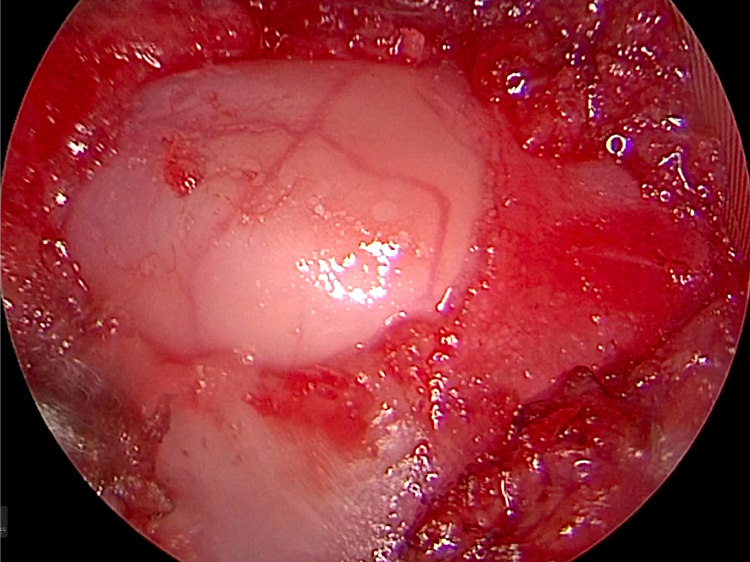

とても小さな2mmのドリル(ラウンドバー)で削っていきます。

とても繊細な手技で神経を使います。せぼねにおよそ6mmほどの穴をあけて椎間板物質をかき出していきます。

右の写真のように使うドリルや鉗子は数mmというとても小さな鉗子を使っていきます。